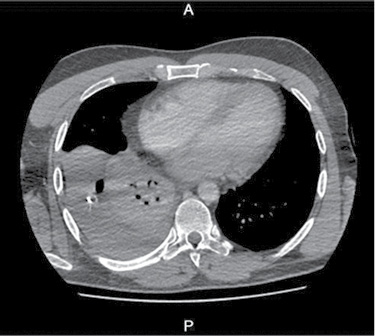

36 m. vyras P. D. atvyko į Gastroenterologijos skyrių patikslinti diagnozės planine kepenų biopsija. Praėjus 8 val. po procedūros, pacientas pajuto maudimą po dešiniuoju šonkaulių lanku punkcijos vietoje. Apžiūros metu pacientas buvo hemodinamiškai stabilus. Atlikus laboratorinius tyrimus, nustatyta saiki anemizacija (hemoglobinas – 128 g/l; norma – 135–160 g/l). Įtariant kraujavimą pilvaplėvėje, atlikta pilvo echoskopija: pilvo ertmėje laisvo skysčio nematyti, dešinėje pleuroje iki 4 cm laisvo skysčio ruožas. Konsultuota krūtinės chirurgo. Rekomenduota atlikti krūtinės ląstos rentgenogramą (Ro). Nustatytas beveik neoringas dešinysis plautis, pastebėta hidrotorakso požymių (1 pav.). Įtarus jatrogeninį hemotoraksą, krūtinės chirurgas atliko diagnostinę pleuros punkciją. Patvirtinus hemotorakso diagnozę, drenuota dešinė pleuros ertmė, išsiskyrė 400 ml kraujo. Tuo metu aktyvaus kraujavimo nenustatyta, hemodinamika išliko stabili, kartotiniuose laboratoriniuose tyrimuose – saiki anemizacija (hemoglobinas – 120 g/l). Atlikus kontrolinę rentgenogramą, nustatytas sumažėjęs skysčio kiekis pleuroje, buvo matyti kompresinių dešiniojo plaučio pakitimų. Įtariant sukrešėjusį hemotoraksą, atlikta skubi krūtinės ląstos KT (2 pav.), kuri patvirtino įtariamą patologiją. Tolesniam operaciniam gydymui pacientas perkeltas į Krūtinės chirurgijos skyrių. Atlikta skubi VATS (angl. video assisted thoracoscopic surgery). Operacijos metu pašalinta 1 000 ml krešulių, aktyvaus kraujavimo nenustatyta, diafragmos kupole rasta nedidelė hematoma. Pooperacinis periodas sklandus (3 pav.). Po trijų dienų geros būklės pacientas išleistas į namus.

3 pav. Krūtinės ląstos priekinė rentgenograma baigus gydymą